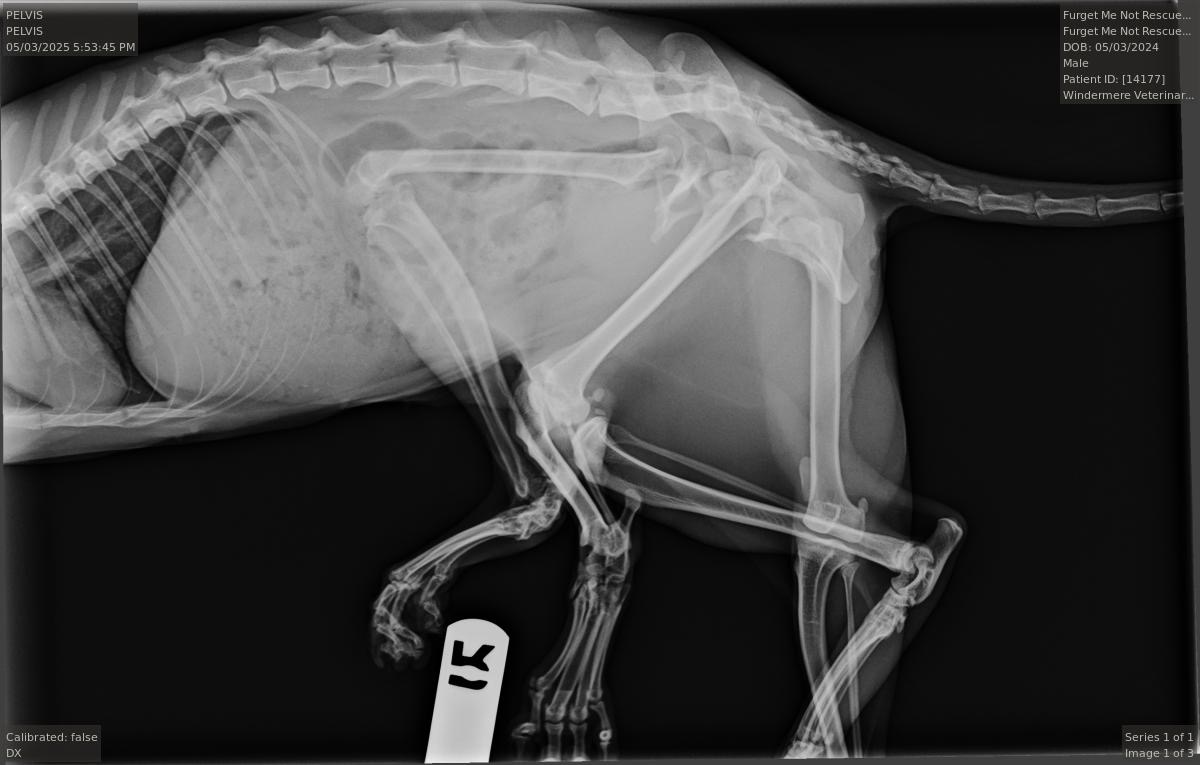

Not only is Bitsy a sweet and beautiful kitty, but she’s one in 1 million. Bitsy has six legs! This condition was most likely caused by absorbing part of her twin in utero. She was born with an extra pelvis and 2 extra legs.

Unfortunately, in addition to her extra legs being atrophied and nonfunctional, her hind leg is also attached to the second pelvis that’s nonfunctioning, and rotated completely backwards, causing her to drag it painfully behind her, covered in sores.